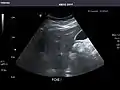

Kidneys: Right and left kidneys measure 11.5 cm and 12 cm in length respectively. No hydronephrosis. Small left lower pole kidney cyst.

Right kidney

Left kidney